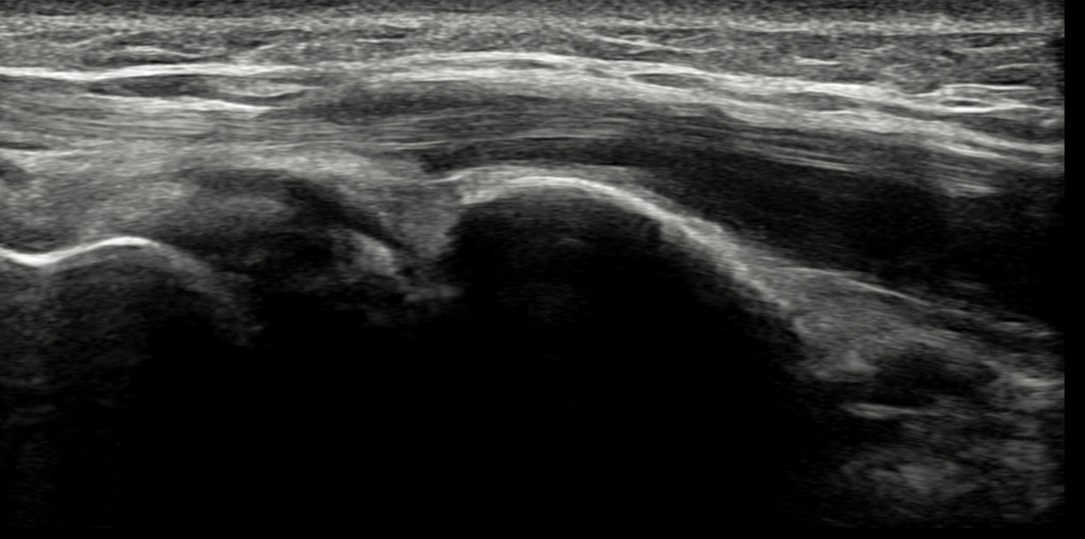

치료 후기에 사용된 전/후 검사 사진은 동일 인물의 결과이며 각 지점 동일 조건에서 촬영되었습니다.

개인에 따라 치료 결과에 차이가 있을 수 있으며, 부작용이 발생할 수 있습니다. 내원 후 충분한 상담을 받으시고 치료를 진행하시면 됩니다.

- 치료기간 : 25 .5 30 . ~ 25 . 6 .27

- 치료횟수 : 5 회(dna 1cycle)

양 손목 신근지대 건초염 & 건염

치료 전

치료 후